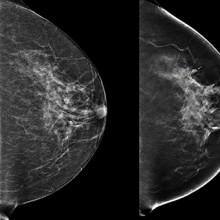

3D imaging technology could improve outcomes for patients with breast cancer

During a conventional digital 2D mammogram, two x-ray images are taken of the breast, one from top-to-bottom and another from side-to-side at an angle. This technology is limited by the overlapping breast tissue that occurs from the required compression of the breast, and breast abnormalities may be hidden. A study at Lawson is looking to determine if digital breast tomosynthesis, a type of 3D imaging, is better at detecting breast tissue abnormalities than the 2D mammography regularly used today. Read more.